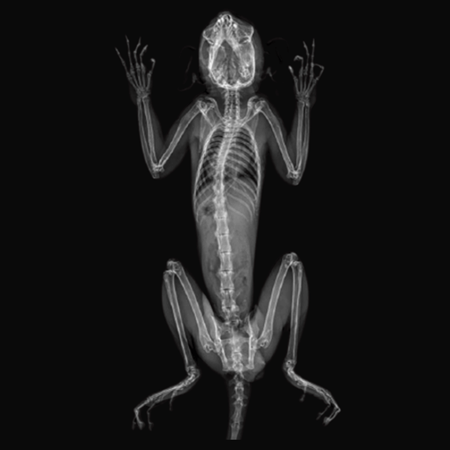

X-Ray Attenuation Image - Rat. Image Credit: Scintica Instrumentation Inc

Bone Mineral Density Image - Rat. Image Credit: Scintica Instrumentation Inc